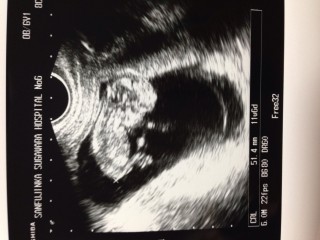

前回(9週目)から倍くらいの大きさになっていて 成長の速さにビックリしました

5・4㎝でした!すくすく育ってくれて嬉しいです♪二週間前より倍近く大きくなってました。